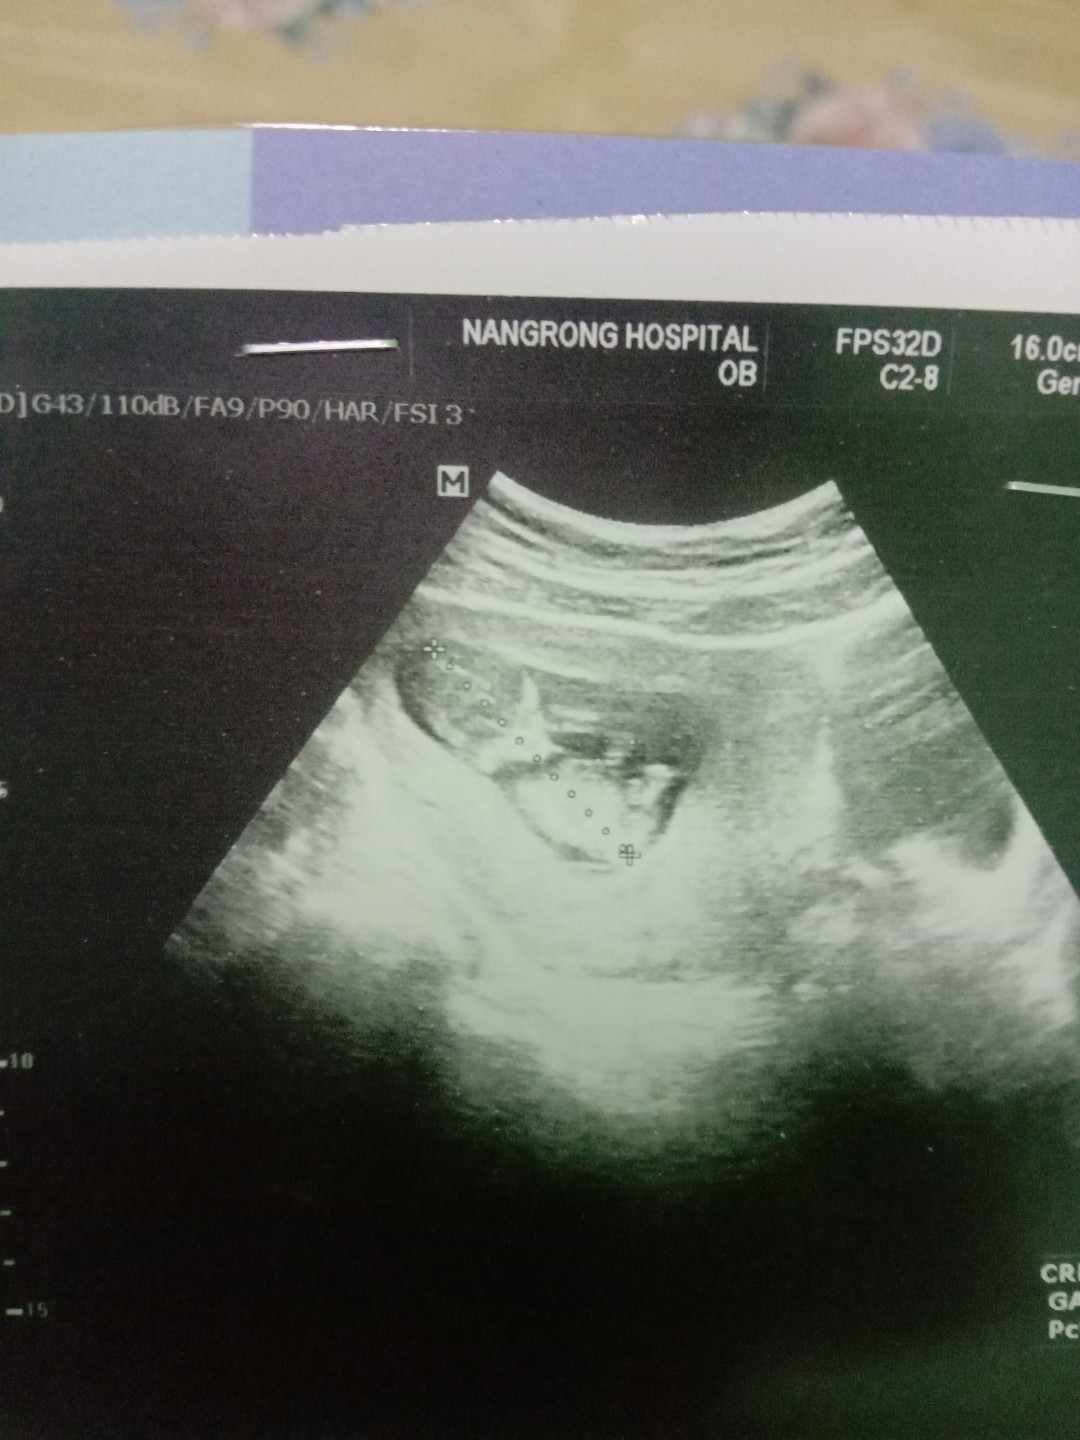

นี่ตอน 12 weeks 4 days ค่ะ ตอนนี้ 19 weeks แล้ว

11weekค่ะ แขนดาเริ่มชัดมาก